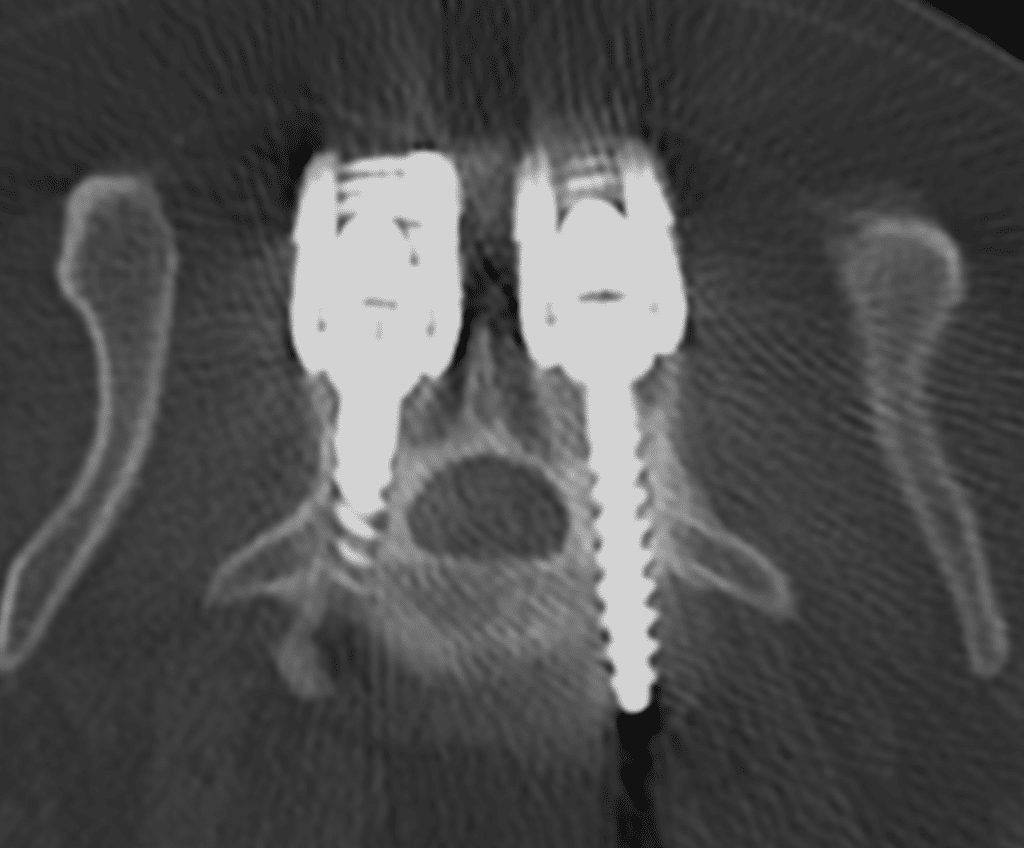

Dr Leblond performed a long but successful surgery on Teebo by placing pedicle screws and rods to stabilise his lumbosacral spine as well as antibiotic sponges to help fight infection.

“In some patients, we have even been able to follow-up the viability of the implants using CT images for several months and demonstrate that the infected bone was growing back filling up the previously infected gap.”